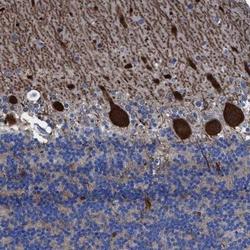

Immunohistochemistry

NBP1-81204 IHC